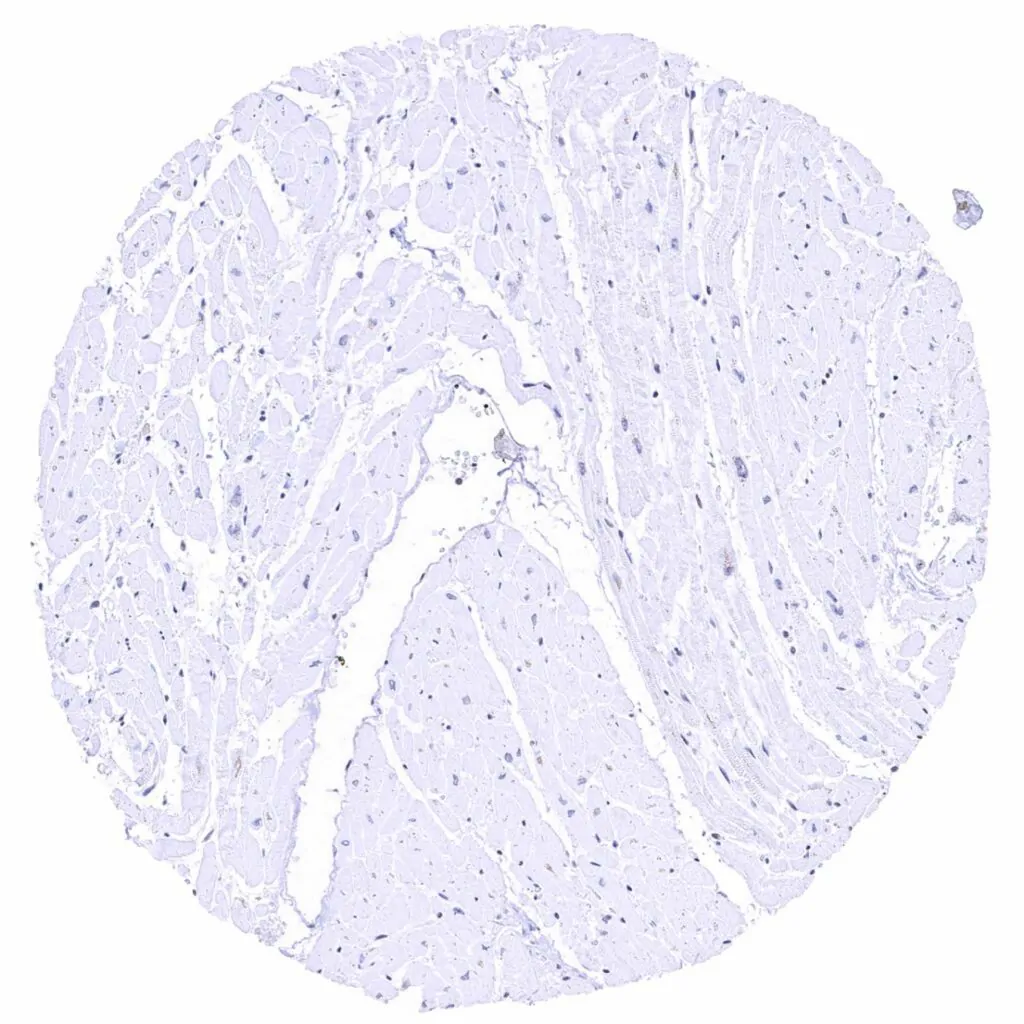

Heart muscle